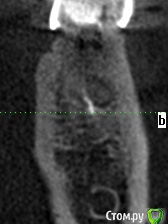

meld Опубликовано 7 ноября, 2017 Поделиться Опубликовано 7 ноября, 2017 Здравствуйте! Чуть больше года назад заболел 36 зуб. Я его пролечил с диагнозом периодонтит. 37 зуба нет. Было принято решение поставить мост с опорой на 36 и 38 зубы. 38 зуб был депульпирован в январе 2017 г. В мае 2017 я поставил мост. Вчера 38 зуб стал болеть при жевании. Боль не сильная, ломящая, через некоторое время проходит. Сегодня съездил в клинику, где лечил зубы, на осмотр. Осмотр ничего не выявил. Сделали прицельный снимок - по словам врачей (а их было двое) криминала тоже нет. Показал им свою томограмму - там тоже (по их словам) ничего нет. Посмотрите, пожалуйста, что не так. СпасибоСрезы 36 зуба Ссылка на комментарий